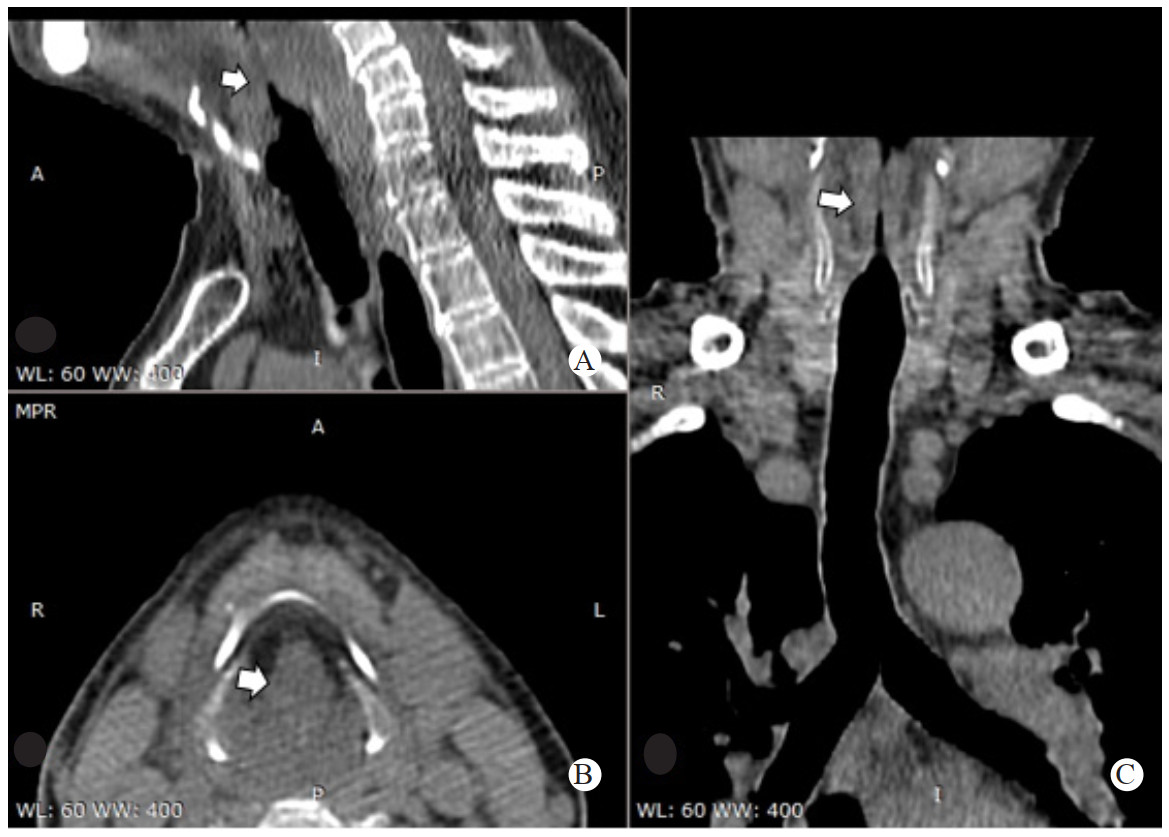

1 病例资料患者,男,58岁,因“咽痛9 h,加重伴胸闷1 h”急诊入院。患者于2020年4月1日下午13时出现咽痛、低热伴全身不适症状,咽部堵塞感。自服头孢拉定、牛黄上清片等药物咽痛症状无好转,18时因咽痛加重,吞咽时疼痛明显,曾尝试再次口服抗生素等药物,但由于吞咽困难持续存在,因此无法吞服。晚间患者咽部疼痛加剧伴流涎,无法忍受吞咽唾液,说话含糊不清,阵发性胸闷不适。遂于22:30至徐州医科大学附属宿迁医院急诊科就诊。急诊室进行体格检查:体温38.8 ℃,急性痛苦面容,扁桃体无明显肿大,咽后壁外观未见明显异常,颈部亦无明显肿胀的迹象,触诊无触痛,心肺听诊未见明显异常。急诊遂行颈、胸部CT及X线检查。颈部及胸部CT提示:会厌皱襞明显增厚伴喉室腔显著狭窄,慢支、肺气肿;颈部X线提示:会厌显著增厚,拇指征阳性(图 1、图 2)。急诊考虑“急性喉头水肿”遂予以急诊留观,给予甲强龙500 mg静脉滴注,同时予吸氧、监护等处理。鼻导管4 L/min时患者的外周血氧饱和度(SpO2)在95%左右。联系耳鼻喉科急诊会诊。

| 矢状位CT扫描, 在室带水平(图A), 双侧咽旁软组织增厚和增强(箭头); 轴位CT扫描, 声门上水平(图B)软组织增厚, 杓状会厌襞和梨状窝区增强; 冠状位CT扫描, 在声门水平(图C)软组织增厚, 延伸至前连合(箭头), 声门和声门上喉部软组织, 增厚、增强并掩盖了咽旁脂肪 图 2 患者颈部CT扫描结果 |

本例患者颈部X线提示会厌显著增厚,拇指征及塔尖征阳性(图 1),计算机断层扫描显示会厌皱襞明显增厚伴喉室腔显著狭窄(图 2)均提示病情危重,为临床干预提供可靠的依据。因此对于重症急性会厌炎的临床特点及危险性应有足够的认识,呼吸困难、流涎、喘鸣和坐直和呼吸困难重症急性会厌炎需要气道干预主要相关因素。本例患者因咽痛、吞咽困难、流涎、说话含糊不清等症状就诊,值班医生亦考虑到会厌炎可能,完善了CT及X线检查后很快出现严重的吸气性呼吸困难,躁动不安,血氧饱和度快速进行性下降,因患者黏痰较多,强迫半坐位无法平躺,在影像确诊后仅数分钟就因气道梗阻发展到心脏骤停。因此遇到在此类重症急性会厌炎患者,在诊治流程上如患者出现吞咽困难、流涎、喘鸣和呼吸困难,应考虑到为需要紧急气道干预患者,紧急送抢救室完善急诊喉镜评估,为建立人工气道缩短时间,避免检查及转运过程中因窒息导致的心搏呼吸骤停。